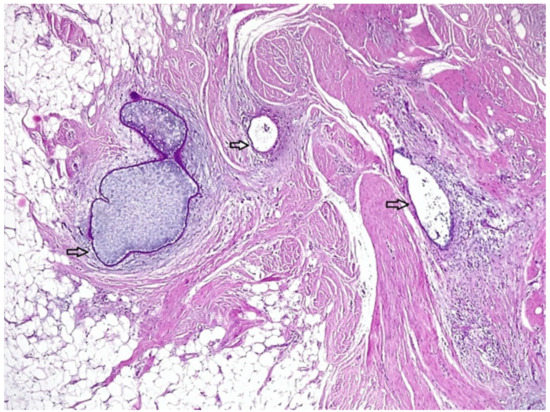

2.2. Case 2